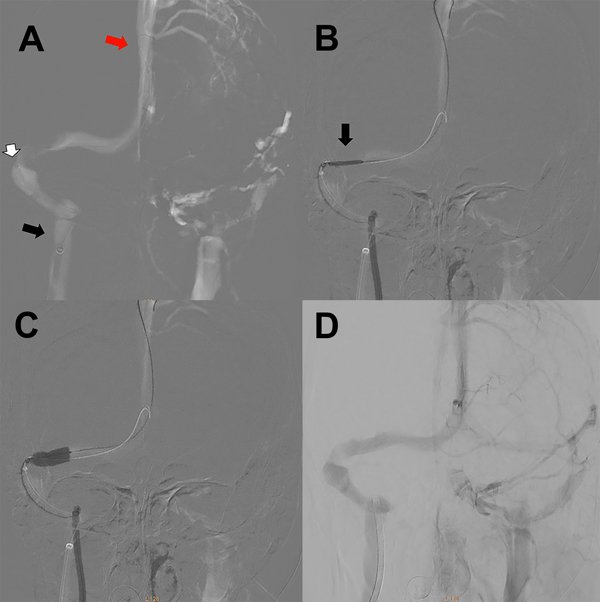

Le indicamos clopidogrel 75mg/día y AAS 100mg/día desde una semana antes del procedimiento. Bajo anestesia general le realizamos un abordaje arterial radial derecho y un abordaje venoso femoral derecho con introductor 5Fr. Se anticoaguló con 10.000 UI de heparina. Bajo guía 0.035 se realizó el recambio del introductor femoral por una vaina carotídea 6Fr progresando la misma hasta el golfo de la yugular derecha. Bajo una guía hidrofílica 0.035 ascendimos un catéter de acceso distal 6Fr hasta el seno sigmoideo derecho (figura 3A). Luego realizamos la angiografía cerebral para determinar el segmento venoso estenosado. Sobre una guía 0.014 localizada en el seno longitudinal superior, bajo roadmap navegamos con técnica rapid exchange un stent balón expandible de cromo-cobalto de 7 por 18mm (Herculink, Abbot) (figura 3B). Una vez localizado el stent a nivel de la estenosis insuflamos el balón con 11 atmósferas hasta llevar el segmento estenosado a diámetros similares a los adyacentes al mismo (figura 3C y 3D). Luego de implantado el stent, realizamos la presurometría del segmento angioplastiado evidenciando un gradiente de presión de 2mm de Hg. Se realizaron todos los controles angiográficos y se retiraron los catéteres arterial y venoso, también se realizó TC de cerebro sin evidencia de complicaciones (figura 4).

Figura 3: A) Imagen angiográfica en modo roadmap incidencia antero-posterior en tiempo venoso. La flecha negra muestra el extremo distal de la vaina carotídea a nivel del golfo de la vena yugular. La flecha blanca indica el extremo distal del catéter de acceso distal en el seno sigmoideo. La flecha roja muestra el extremo distal de la microguía 0.014 a nivel del seno longitudinal superior. B) Imagen angiográfica en modo roadmap incidencia antero-posterior en tiempo venoso. La flecha negra muestra el stent balón localizado en la posición de la estenosis previo a la impactación del mismo. C) Imagen angiográfica en modo roadmap incidencia antero-posterior en tiempo venoso. El balón ya fue inflado en el sitio de la estenosis. D) Angiografía cerebral digital con adquisición frente en tiempo venoso luego de la impactación del stent en el seno transverso derecho sin estenosis residual.